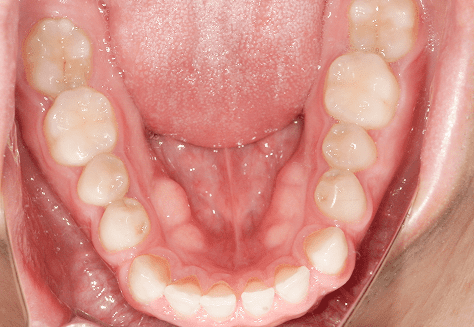

M.H

治療前

治療後

主訴

前歯が出ている。下の歯並びが特に気になる。奥歯でしっかり噛めない。

診断

上顎前突・叢生・シザーズバイト

年齢/性別

20代/男性

抜歯部位

下顎両側大三大臼歯(口腔外科にて)

上顎両側第一小臼歯・下顎左側側切歯

(当院にて5,500円×3) -

使用装置

上下エッジワイズ→インビザライン(PBM使用)

保定装置

上下ビベラリテーナー

料金

初回資料採得・・・・・・・30,000円

診断料・・・・・・・・・・33,000円

動的治療終了時資料採得・・5,500円 -

基本料金

880,000円

診察料金

5,500円×44回

治療期間

3年6カ月